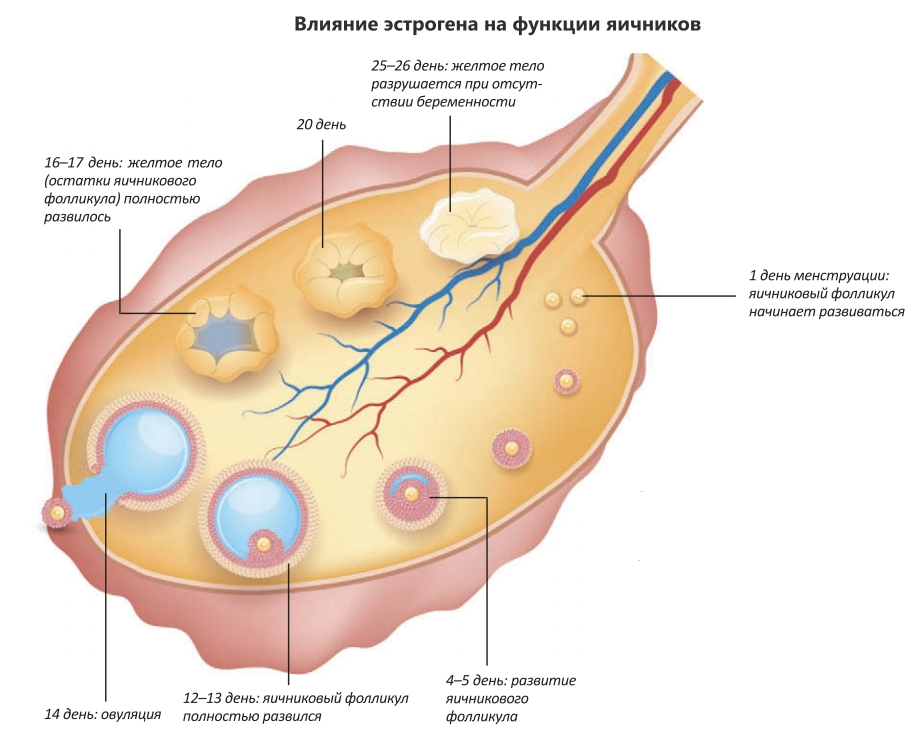

Созревание фолликула в яичнике: этапы и процессы